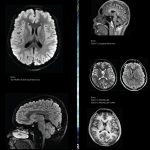

Bu cihazla ileri düzey MR tetkiklerin hemen hepsi yapılabilmektedir. Kardiyak MR, MR Spektroskopi, Fonksiyonel MR, Perfüzyon MR, MR Artrografi, Tüm Vücut MR, Meme MR, Multiparametrik Prostat MR gibi ileri teknoloji gerektiren tüm incelemeler GE Signa Explorer ile gerçekleştirilebilmektedir.

Cihazın bir başka özelliği olan fokus çekim ile hastanın vücudundaki herhangi bir bölgeye odaklanılarak ilgili alanın detaylı görüntüleri alınabilmektedir. Bu imkan, tanıdaki doğruluk oranlarını belirgin derecede arttırmaktadır.

Hastaların vücutlarında herhangi bir nedenle bulunan metalik parçalar, bilindiği gibi MR çekiminde artefakt oluşturmaktadır. Bu nedenle ilgili bölgenin değerlendirilmesi neredeyse imkansız hale gelmektedir. Oysa bu cihaz metalik artefaktların yarattığı görüntü bozukluğunu büyük ölçüde ortadan kaldırmaktadır. Böylece radyoloji hekiminin işi son derece kolaylaşmakta ve ilgili bölgenin tanı konulabilir hale gelmesi sağlanmaktadır. Bu teknoloji, hekimler için çok kıymetli bir imkandır.

Önemli özelliklerden birisi de hareket düzeltme teknolojisidir. Çekim sırasında hastanın cihazda hareketsiz durması görüntü kalitesi açısından son derece önemli olmasına rağmen, bazı hastalarımız çeşitli nedenlerle, istemsiz olarak hareketsiz duramamaktadır. Hareket ile görüntü bozulduğu için tanı koyma imkanımız zorlaşmaktadır. Fakat bu yeni özellik ile çekim sırasında oluşan hareketler büyük ölçüde düzeltilerek; hareketsize yakın bir görüntü sunulmaktadır. Bu fonksiyon, özellikle çekim sırasında cihazda hareketsiz durmaları çok zor olan çocuk hastalarımız için önemli bir yenilik olarak kullanılabilmektedir.